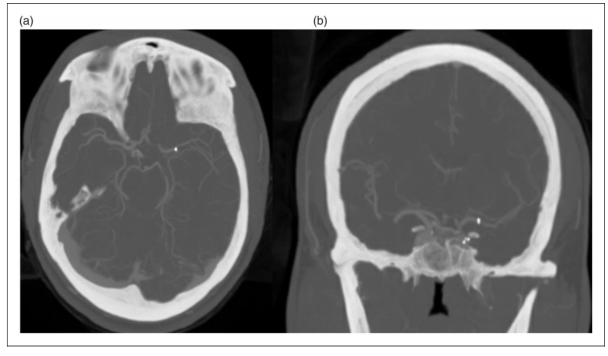

患者在整个围手术期未出现明显症状,并正常出院。在六个月随访中,患者神经系统没有遗留并发症。一年的CTA随访显示支架部位没有再狭窄(图3)。

图3